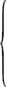

367Sarcoptes scabiei. (After Fürstenberg)518

368Sarcoptes scabiei: male, ventral aspect. (After Fürstenberg)519